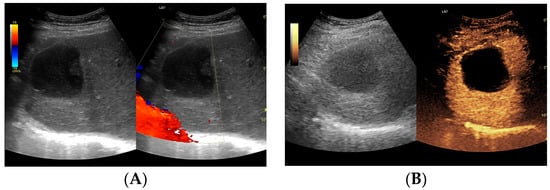

Utility of Contrast-Enhanced Ultrasound in Optimizing Hepatic Abscess Treatment and Monitoring

3. Results

3.2.1. Arterial Phase

3.2.2. Early Venous Phase

3.2.3. Late Venous Phase